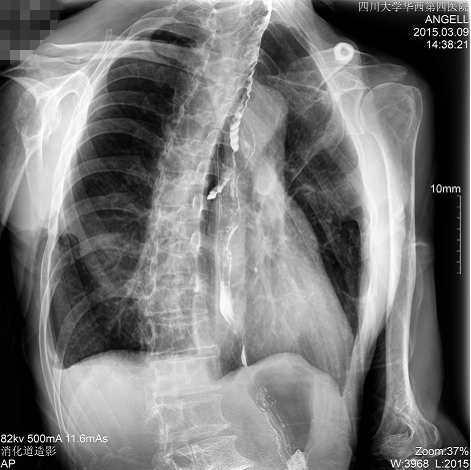

如下圖所示:該患者因吞咽時感到很難受,進食時也經(jīng)常咳嗽故就醫(yī)診斷。使用多功能dr為病人進行消化道造影診斷,要求他吞鋇后發(fā)現(xiàn),食道各段通過順利,形態(tài)規(guī)則,雙側(cè)梨狀窩不對稱左側(cè)稍淺,多次吞咽動作后,仍見鋇劑滯留,并見鋇劑進入氣管,屬于會厭征陽性。會厭功能紊亂,鋇劑進入了氣管。

圖為斜位:通過動態(tài)影像可以清楚看到鋇劑進入了支氣管道

通過多功能dr可以診斷該病人的癥狀為會厭功能紊亂,鋇劑進入到了氣管。而在動態(tài)透視下可以清晰的觀察到鋇劑從何處進入氣管,可清晰顯示食管粘膜結(jié)構(gòu)。使用多功能dr其獨特的視頻采集技術(shù),可實時保存視頻并能實現(xiàn)900萬像素實時點片,才能獲取這樣清晰的病灶點。而常規(guī)dr只能拍攝靜態(tài)片,且成像效果大打折扣,因此較難確診病灶。